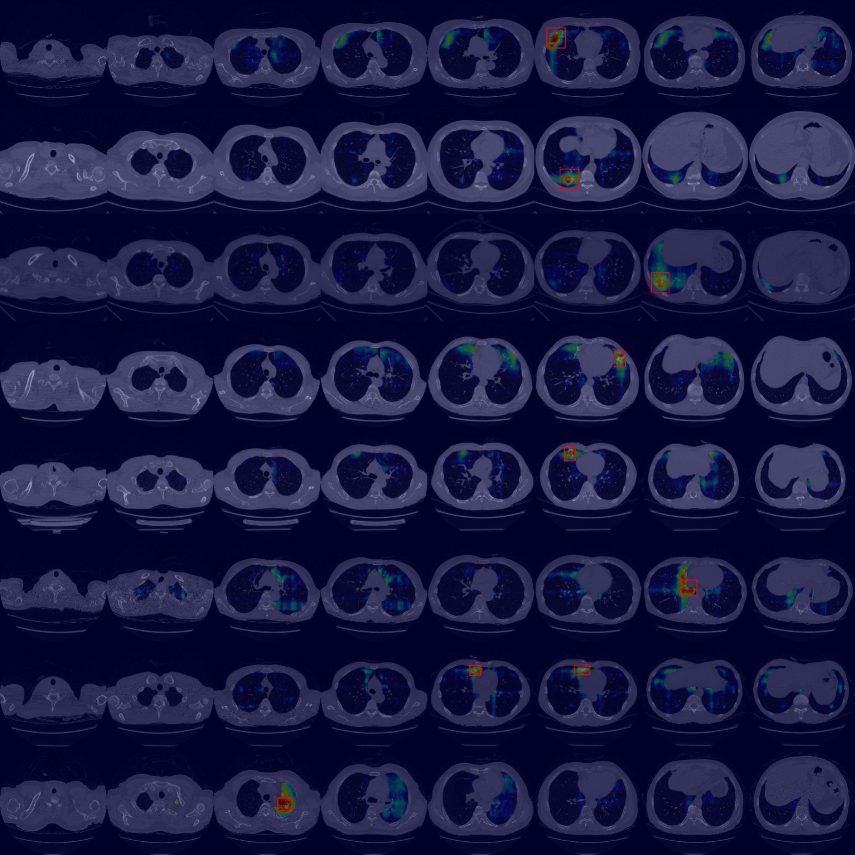

By using the internal clinical dataset from SMC of pneumonia and tuberculosis cases, we experimentally verified the superiority of the proposed VMPR-UAD through various comparative experiments. We also provide quantitative results and 3D abnormal (lesion) localization/visualization results of VMPR-UAD using the internal dataset for pneumonia and tuberculosis in the Supplementary Material to illustrate the superiority of anomaly localization by VMPR-UAD.

Finally, we evaluated the 3D abnormal (lesion) localization performance of the proposed VMPR-UAD. Of the 63 cancer cases in the MSD dataset with ground-truth annotations available, we excluded two cases (cases 38 and 96) of incorrect annotation or showing other diseases. We calculated whether the cancer area predicted by VMPR-UAD (binarized at a certain high-probability threshold) overlapped with the annotated cancer area. As a result, 57 of the 61 cases showed overlapping, demonstrating that VMPR-UAD can localize 3D lung anomalies (cancer in this case) with an accuracy of 93. Some localization examples in 3D data are shown in Fig. L. The red points in Fig. L(b) show the 3D cancer locations that the proposed method estimates with the highest confidence (i.e., location of highest pixel value in the 3D anomaly map). The red points in Fig. L(a) show the ground-truth cancer location. The ground truth and prediction shown in Fig. L confirm that VMPR-UAD correctly finds the lung anomaly 3D region. More detailed visualization results are available in the Supplementary Material. The prediction consistency can also be observed in 2D slices, as shown in Fig. M, where our anomaly localization map indicates correct cancer regions. Hence, the proposed VMPR-UAD can automatically localize or segment lesions without requiring any lesion information (i.e., using only CT slices from healthy subjects) for training.